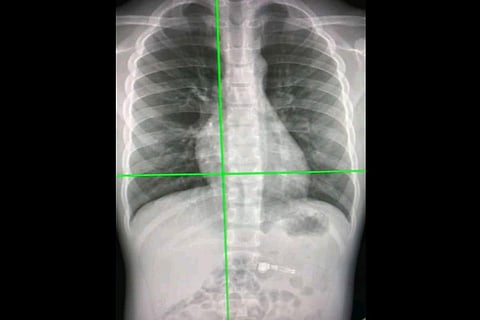

Australian researchers have developed an artificial intelligence (AI) system that can rapidly detect COVID-19 from chest X-rays with more than 98 percent accuracy and may be more beneficial than the currently used RT-PCR test. According to Professor Amir H. Gandomi from the University of Technology Sydney (UTS) Data Science Institute, there was a pressing need for effective automated tools to detect COVID-19, given the significant impact on public health and the global economy.

"The most widely used COVID-19 test, real-time polymerase chain reaction (PCR), can be slow and costly and produce false negatives. To confirm a diagnosis, radiologists need to manually examine CT scans or X-rays, which can be time-consuming and prone to error," said Professor Gandomi.

"The new AI system could be particularly beneficial in countries experiencing high levels of COVID-19 where there is a shortage of radiologists. Chest X-rays are portable, widely available, and provide lower exposure to ionizing radiation than CT scans," he said.

Common symptoms of COVID-19 include fever, cough, difficulty breathing, and a sore throat, but it can be difficult to distinguish COVID-19 from flu and other types of pneumonia. The new AI system, detailed in a paper published in the journal Scientific Reports, uses a deep learning-based algorithm called a Custom Convolutional Neural Network (Custom-CNN) that is able to quickly and accurately distinguish between COVID-19 cases, normal cases, and pneumonia in X-ray images. "Deep learning offers an end-to-end solution, eliminating the need to manually search for biomarkers. The Custom-CNN model streamlines the detection process, providing a faster and more accurate diagnosis of COVID-19," said Professor Gandomi.

"If a PCR test or rapid antigen test shows a negative or inconclusive result, due to low sensitivity, patients may require further examination via radiological imaging to confirm or rule out the virus's presence. In this situation, the new AI system could prove beneficial,” he added. The custom-CNN model was evaluated via a comprehensive comparative analysis, with accuracy as the performance criterion. The results showed that the new model outperforms the other AI diagnostic models, the team said.